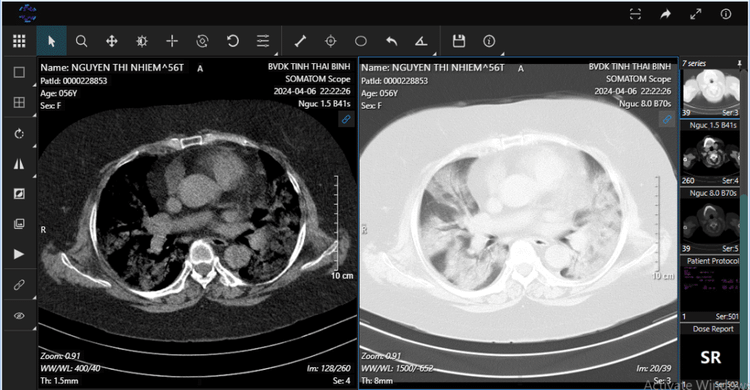

| Hình ảnh chụp CLVT phổi bệnh nhân khi vào viện - Ảnh BVCC |

Bệnh nhân được chuyển đến khoa HSTC – CĐ, BVĐK tỉnh Thái Bình trong tình trạng khó thở dữ dội, tím tái, Sp02 80%, chụp cắt lớp vi tính (CLVT) lồng ngực có hình ảnh tổn thương lan tỏa gần hết 2 phế trường, xét nghiệm khí máu có tình trạng giảm oxy máu rất nặng (PaO2/FiO2 = 71).

Bệnh nhân được chẩn đoán: Viêm phổi ARDS do Covid-19/suy tim, tăng huyết áp, đái tháo đường type 2, suy thượng thận, rối loạn chuyển hóa lipid máu.